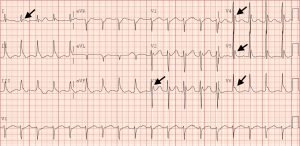

The initial EKG shows marked elevation of the J-point (point where the QRS segment joins the ST segment), otherwise known as an “Osborn Wave” (see black arrows). A subsequent EKG obtained after active rewarming, showed resolution of the Osborn waves.

Osborn waves can be a predictor of mortality in certain situations including hypothermia and acute coronary syndrome.2,5 Reports have demonstrated an inverse relationship between the amplitude of Osborn waves and core body temperature: the waves increasing in amplitude with lower body temperatures. These waves often return to baseline as the body is rewarmed. There are, however, multiple determinants of Osborn waves and they do not strictly correlate with body temperature.6